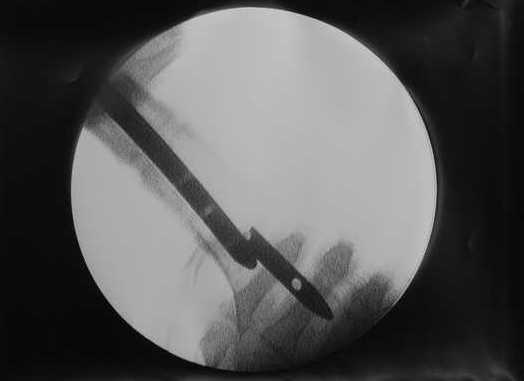

Спицы оставлять не надо. Надо их убрать, но перед этим ввести винт-poller. Такая необходимость возникает в редких случаях, когда можно ожидать смещения длинного отломка. Спицы из короткого отломка после введения запирающих винтов можно удалять без риска смещения.

В приложении пример, дистальный отломок пружинил кзади. Два винта потому, что первый оказался чуть кпереди и не упирался в гвоздь.